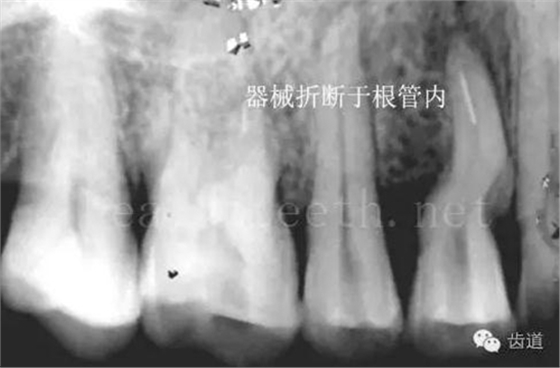

長期戴活動義齒不當或是戴不良修復(fù)義齒造成的口腔粘膜潰瘍,應(yīng)該引起高度警惕,因為這種潰瘍?nèi)菀装┳?/span> 黑毛舌 舌息肉,該患者同時伴有胃、食管息肉,后來看內(nèi)科了,具體情況不詳 四、孩子的牙齒問題 乳牙未退,牙根穿出牙齦對上唇粘膜造成刺激 乳牙滯留,也是孩子在退牙過程中最容易遇到的問題 五、牙齒發(fā)育上的問題 變色牙 氟斑牙 釉質(zhì)發(fā)育不全 四環(huán)素牙 牙神經(jīng)治療后的牙齒變色 10歲孩子剛剛萌出的牙齒變色 2、埋伏牙 左上乳3滯留,恒3未見萌出,曲面斷層片顯示牙齒埋伏 通過CT片確定埋伏牙齒具體的位置,顯示距離左側(cè)上頜竇很近,偏唇側(cè),這為手術(shù)定位提供了方便 手術(shù)中切斷、完整拔出,未損傷上頜竇 其他埋伏牙 3、多生牙 病例1 病例2 病例3,同時多生兩顆牙齒 4、各種畸形牙 畸形過小牙 融合牙:恒牙和乳牙都可以發(fā)生融合的情況(兩顆牙齒長在了一起) 畸形中央尖:在牙齒的中央,兩個牙尖之間又多長出一個牙尖,由于進食的磨耗很容易造成磨穿,神經(jīng)就會與外界相通,出現(xiàn)牙髓炎的癥狀 六、牙齒的外傷 牙冠折斷 牙根折斷 烤瓷牙打樁修復(fù)后牙根折斷 外傷后牙齒的全脫位,應(yīng)該保留牙齒盡早做再植手術(shù) 七、牙齒的慢性損傷 牙頸部楔狀缺損 牙冠劈裂及完整拔除后的情況 牙根縱裂及拔除后的情況 牙隱裂,牙齒表面有肉眼看不到的裂紋,細菌通過其進入牙髓,容易出現(xiàn)牙髓炎癥狀,嚴重可以造成牙齒的劈裂 這是一位來中國學(xué)習(xí)的俄羅斯大學(xué)生的牙齒,已經(jīng)做過了根管治療,牙齒咬合面有隱裂,通過鋼絲結(jié)扎固定,做鑄造金屬冠修復(fù)。 八、牙髓炎、根尖周炎 下面圖片都是慢性根尖周炎的病例,有了齲齒,進一步發(fā)展就是牙髓炎,如果此時沒有得到及時的治療,疾病會逐漸發(fā)展破壞到根尖的骨質(zhì),將骨質(zhì)破壞后就在牙齦上出現(xiàn)一個膿瘺,此時患者不再感覺到牙齒的疼痛了,往往忽視了治療,但是這種不痛并不是疾病好轉(zhuǎn)了,而是因為疾病的炎性滲出得到了引流,這個膿瘺會出現(xiàn)有時候變大了,有時候又變小了,但是如果不治療是不會自己愈合的,只有經(jīng)過完善的根管治療后才有好轉(zhuǎn)的可能,但是在疾病的治療中時間是起決定作用的,時間拖得越晚,好轉(zhuǎn)的可能性越小,經(jīng)過根管治療后如果膿瘺還是沒有消失,就需要做根尖刮治術(shù),如果仍然沒有好轉(zhuǎn),就只能做根尖切除術(shù)了,這對牙齒的穩(wěn)固是不利的。下面圖片中在膿瘺中插入了一個牙膠尖,是我們做根管充填用的材料,是非常軟的,就是在口腔牙齦瘺管的地方插進去,通過拍牙片可以清晰地看到它到達的位置,從而確定發(fā)病的牙齒,此處是為了讓大家看得更清楚。 門牙兩個膿瘺 烤瓷牙修復(fù)后牙齦出現(xiàn)兩個膿瘺,插入牙膠尖,牙片顯示牙膠尖到達的位置就是根尖炎癥的位置,根尖骨質(zhì)密度降低(發(fā)黑的地方) 牙齒根尖膿瘺,治療前、中、后的圖片對照,完善根管治療后膿瘺明顯消失了 牙髓炎和根尖炎治療的關(guān)鍵就是根管治療 合格的根管充填治療 不良的根管充填治療 九、關(guān)于智齒(第八顆牙) 四顆長不出來的智齒 智齒反復(fù)發(fā)炎造成的頰瘺,膿腫切開引流后面部會留疤 智齒造成的頜骨囊腫,手術(shù)切除后需要植骨 十、各種錯合畸形 開合 深覆合 深覆蓋,上頜前突 反合(地包天) 牙齒排列擁擠 來源:牙醫(yī)愛看的 KQ88口腔醫(yī)學(xué)網(wǎng)